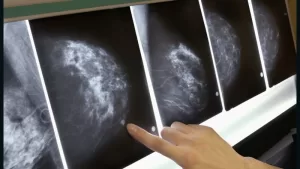

Breast Cancer Screening: Assessing the Pros, Cons, and Accuracy of Mammograms

As you consider your health and preventive care options, breast cancer screening through mammography is likely a topic that has crossed your mind. Mammograms have long been touted as an essential tool for early detection, potentially saving lives through timely intervention. However, recent debates have emerged regarding their efficacy and potential drawbacks. This article aims to provide you with a comprehensive overview of mammogram screening, exploring both its advantages and limitations. By examining the latest research and expert opinions, you’ll gain valuable insights to help inform your decision-making process regarding this important aspect of women’s health.

Mammograms play a crucial role in breast cancer screening, offering significant advantages for early detection. The primary benefit is the ability to identify tumors before they become palpable, allowing for timely intervention and improved treatment outcomes. Studies have shown that regular mammography can reduce breast cancer mortality rates by 20-40% in women aged 40-69 years. This screening method is particularly effective for detecting small, early-stage cancers, which are often more treatable and may require less aggressive therapies. While considering the pros and cons of breast cancer screening, it’s important to note that mammogram accuracy has improved over time, with 3D mammography offering even greater precision in some cases.